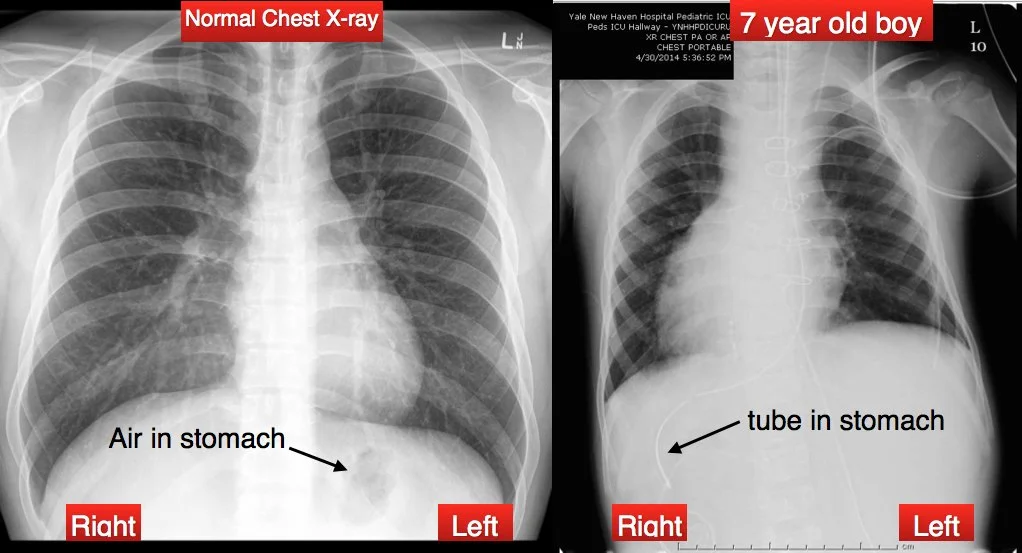

Radiograph of normal and heterotaxic anatomy